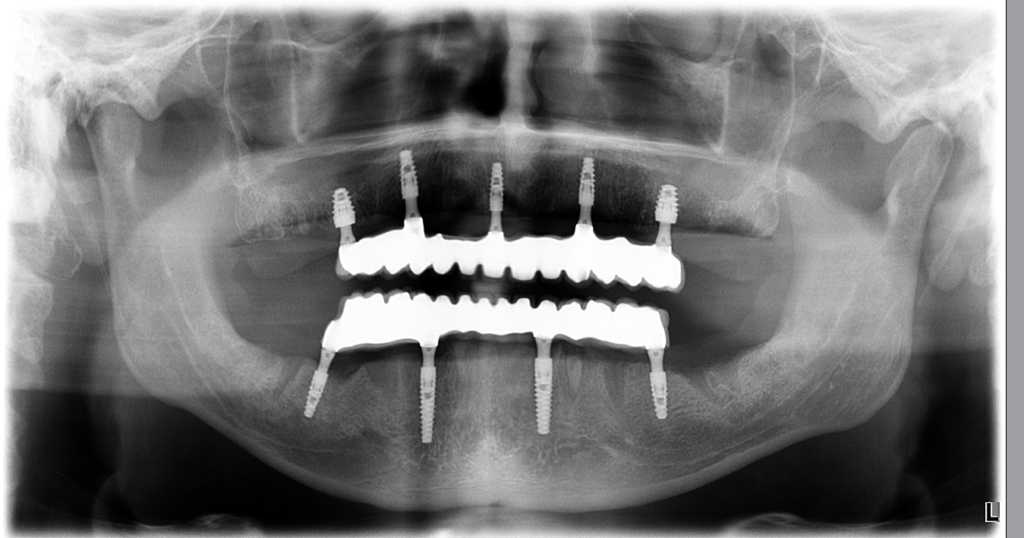

5 implantátov v hornej čeľusti a 4 implantátov v dolnej čeľusti, ktoré nesú 12 korunkových zubov ( teda mostík ) hore a 12 dole.

Nebolo potrebné zavádzať riešenie „6/14“ zvolili sme šetrnejší plán, ktorý splnil všetky potreby pacienta.

RTG snímka zas potvrdzuje stabilitu implantátov a zdravé okolité tkanivá.